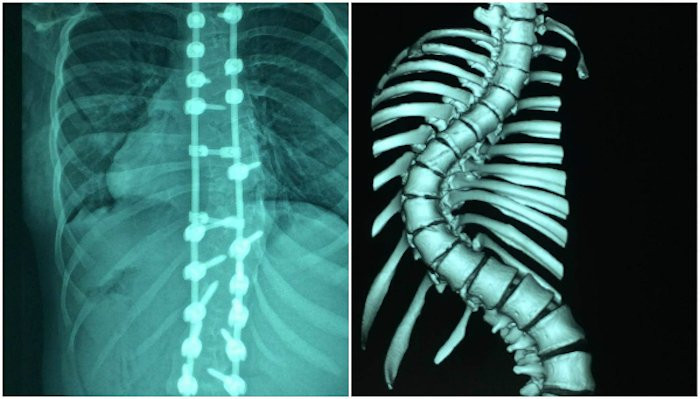

Cột sống bệnh nhân sau khi phẫu thuật và trước đó.

Ngày 26/12/2017, các bác sĩ tiến hành cuộc phẫu thuật kéo dài 6,5 giờ để nắn chỉnh, hàn xương giúp thay đổi hình dạng cột sống. Bé được bắt 21 ốc, 2 thanh nối dọc, 2 thanh nối ngang để cố định cột sống. Bệnh nhân mất khoảng 850 ml máu, được sử dụng kỹ thuật truyền máu hoàn hồi, sử dụng lại chính lượng máu mất để truyền.

"Thường cột sống cong trên 100 độ, tỷ lệ nắn chỉnh đạt được trên 40% là tốt. Trường hợp này bệnh nhân được nắn chỉnh, sửa chữa trên 64%", giáo sư Thành phân tích. Chiều cao bệnh nhân tăng thêm 7 cm, từ 1,48 m trước mổ lên 1,55 m.